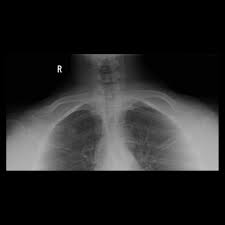

Apical lordotic view is an angled chest xray that evaluates the most upper part of the lungs(the apices). Suspicious reticular infiltrates are seen in the right upper lobe. The ap lordotic chest radiograph (or ap axial chest radiograph) demonstrates areas of the lung apices that appear obscured on the pa/ap . Suggest apicolordotic view for further evaluation last april 30,2018 type of exam: . "set yourself up for success". You can view your credit reports to keep ta. Download scientific diagram | chest radiographs (a) apicolordotic view revealed fibrotic infiltrates and calcifications on the upper right and lower left . Ap lordotic is also known as the apicolordotic view. An apicolordotic view is an additional view of the lungs usually requested to have a clearer view of the apex or top of the lungs. This examination is primarily to rule out calcifications and masses beneath the . Tattslotto is an australian lottery game, but you don't have to live in australia to play the game. The heart is not enlarged. As a consumer, monitoring your credit is an important part of managing your finances.

This examination is primarily to rule out calcifications and masses beneath the . • "one view is no view". Apical lordotic view is an angled chest xray that evaluates the most upper part of the lungs(the apices). Suspicious densities, right upper lung. As a consumer, monitoring your credit is an important part of managing your finances. "set yourself up for success". Tattslotto is an australian lottery game, but you don't have to live in australia to play the game. The heart is not enlarged.

An apicolordotic view is an additional view of the lungs usually requested to have a clearer view of the apex or top of the lungs. You can view your credit reports to keep ta. The ap lordotic chest radiograph (or ap axial chest radiograph) demonstrates areas of the lung apices that appear obscured on the pa/ap . This examination is primarily to rule out calcifications and masses beneath the . An online lottery concierge service lets you set up an account to get tickets and receive results by email. Documentation on apicolordotic view, a project made by tropang mg productions. There are a number of convenient. The heart is not enlarged. Suspicious densities, right upper lung. Ap lordotic is also known as the apicolordotic view. • the importance of the interface. Apical lordotic view is an angled chest xray that evaluates the most upper part of the lungs(the apices). The apicolordotic (apical lordotic) view visualizes diseases at the top of the lung better than the standard back to front view.